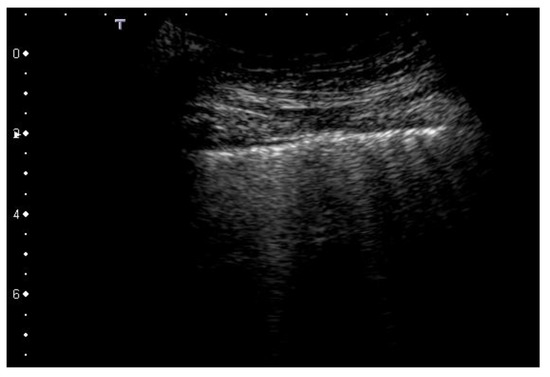

| 2 | Pleural line has relevant alterations. Progression of subversion of peripheral air space geometry causes a predominance of vertical artifacts. Small subpleural consolidations, related to deaeration, can be present. |